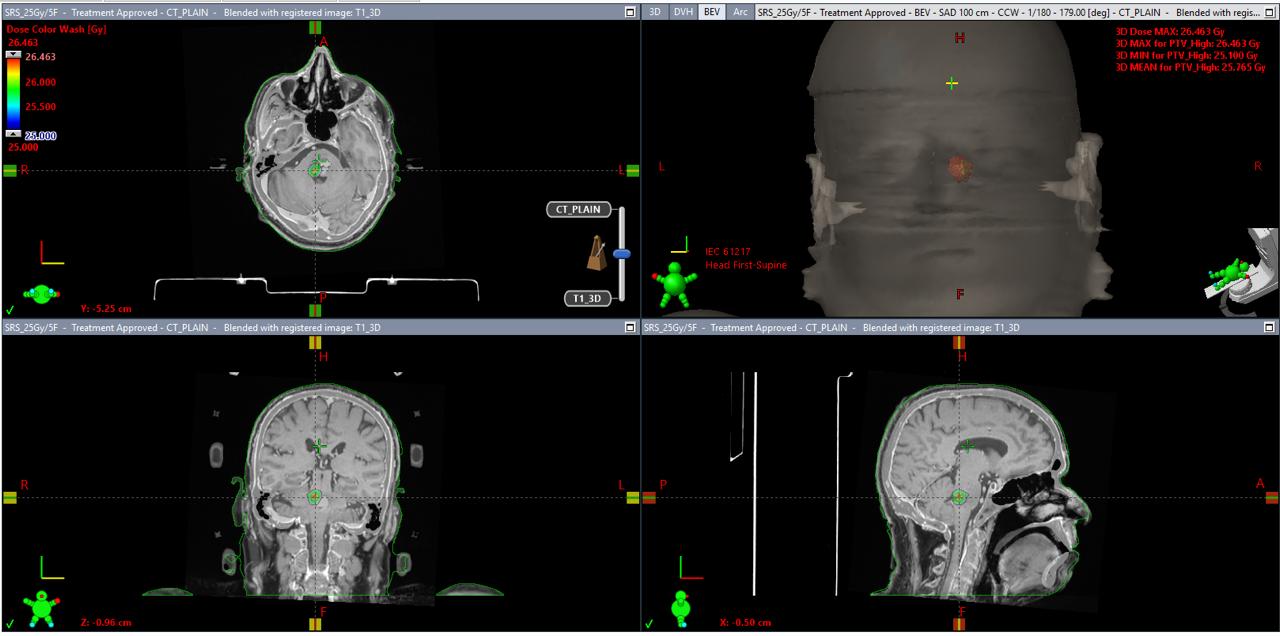

dose-volume-histogram-dvh-beams-eye-view-bev-for-srs-treatment

The patient received:

• 5 SRS sessions (fractions)

• Total dose: 25 Gy

• 5 Gy per session